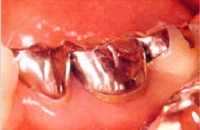

金属が入っている状態

奥歯に金属の歯が入っている状態です。

金属を長年使用していると、唾液で成分が溶けだし、金属アレルギーを引き起こすこともあります。

また、口臭の原因にもなります。